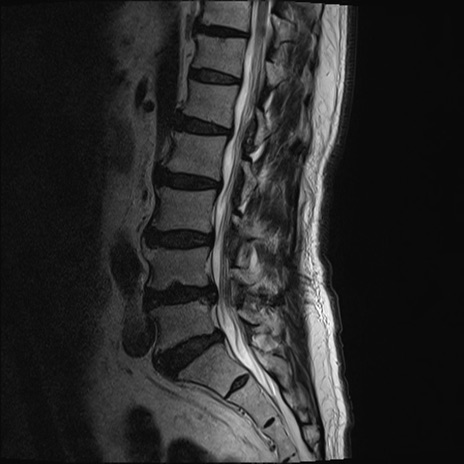

【整形】TIPS症例2 腰椎MRI T2WI(矢状断像)

【症例】70歳代男性

【主訴】左下肢痛

【現病歴】2週間前くらいから腰痛、左下肢痛あり。左臀部から大腿、下腿外側のしびれが常時ある。歩行とともに同部位の痛みあり。

【身体所見】Lasegue70-/60+、Bragard-/±、PTR ±/±、ATR -/-、IP 5/5、TA 5/4、TS 5/5、EHL 右第1足趾なし/3、FHL 5/5、hypersthesia(-)、足背動脈触知良好

異常所見と診断は?